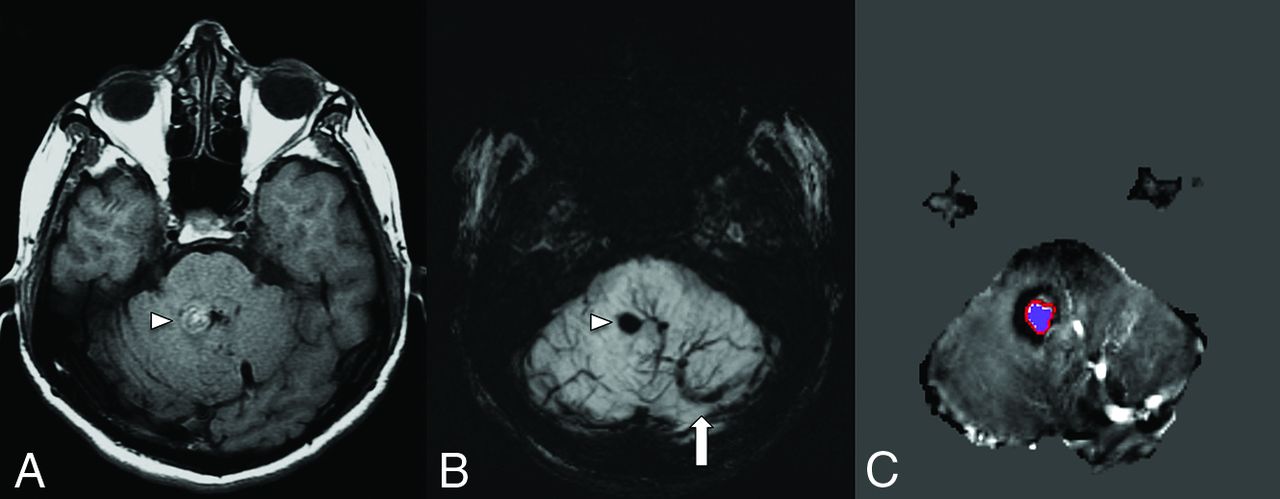

CVMS in a patient with a left orbital venous malformation depicted on the coronal T2-weighted fat saturated (A) and coronal post-gadolinium-enhanced T1-weighted fat saturated (B) images, which show an infiltrative T2-weighted hyperintense intraconal lesion with avid contrast enhancement (asterisk). Coronal gadolinium-enhanced T1-weighted image (C) reveals a large left basal ganglia DVA (arrow) with the collector vein draining in the left superior petrosal sinus.